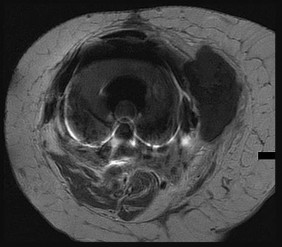

Figures 6a through 6d are the radiographs and T1-weighted sagittal and fat-saturated axial MR images of an otherwise healthy 56-year-old man who has anterior knee pain and intermittent swelling after sustaining a noncontact twisting injury. Low-power and high-power hematoxylin and eosin stained histologic specimens are shown in Figures 6e and 6f. Based on the history, radiographs, CT scan, MR imaging, and histologic findings, what is the most likely diagnosis?

The lesion in the posterior intercondylar knee notch is a benign synovial hemangioma. Intralesional calcifications, classically associated with hemangiomas, are frequently not identified on plain radiographs. The MR imaging reveals a hypervascular lesion with multiple filling defects, with hyperintensity on T2-weighted images and low-to-intermediate signal intensity on T1-weighted images. Histologically, vascular lakes within fine capillaries with a synovium on the surface of the lesion are characteristic of this condition. Many patients with synovial hemangioma have pain, swelling, stiffness, or mechanical symptoms. The correlation of symptoms with the hemangioma for this patient is unclear because there was recent trauma and a concurrent meniscus tear. Simultaneous treatment of both potential sources of pain is typically recommended. As with PVNS, the disease can be localized or diffuse. Surgical excision, either open or arthroscopic, is the recommended treatment. PVNS is the most common intra-articular tumor, but hypointensity in either the diffuse or localized type is characteristic in both T1- and T2-weighted images. Synovial sarcoma, although often found close to a joint, is not characteristically found within a joint.